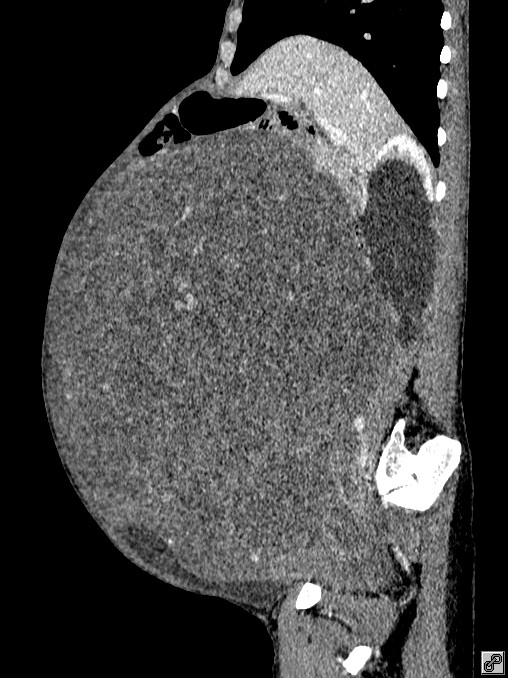

意识到有问题,家人赶紧带着王阿姨来到广医三院看病。随后,检查结果震惊了家人——王阿姨的子宫长了一个巨大的肿物,占满了整个盆腹腔!医生初步判断可能是子宫肌瘤。

手术前患者的CT影像图。

“子宫肌瘤很常见,但如此巨大的肌瘤比较少见”接诊的妇科主任生秀杰介绍:“巨型肿物在盆腔内生长,不停‘吸取’身体的营养,让身体长期处于消耗态势,导致了患者越来越消瘦。此外,肿物也压迫影响了盆腹腔多个脏器,如果继续发展,很可能进一步膈肌上抬,患者呼吸都会受限。”